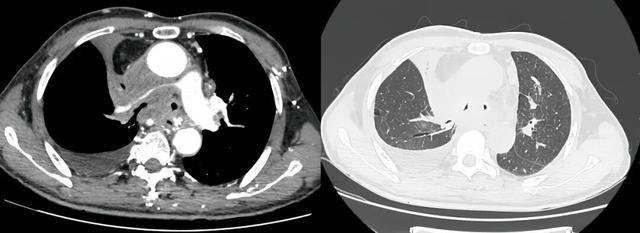

手术过程